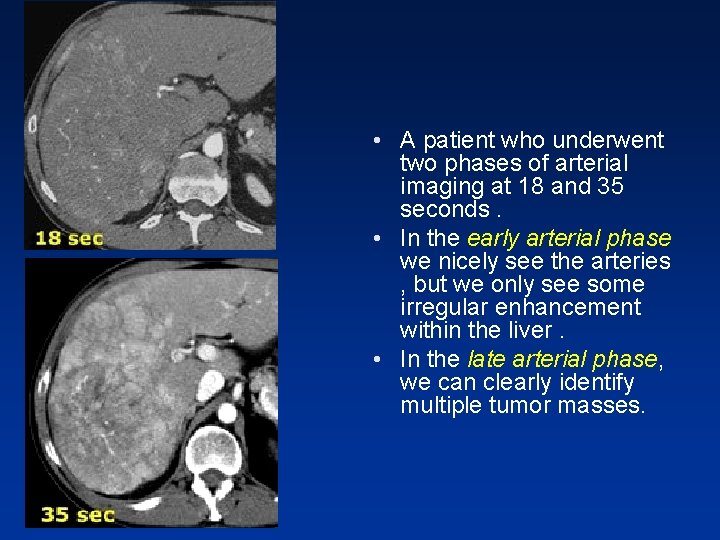

• A patient who underwent two phases of arterial imaging at 18 and 35 seconds. • In the early arterial phase we nicely see the arteries , but we only see some irregular enhancement within the liver. • In the late arterial phase, we can clearly identify multiple tumor masses.

• Notice that in the late arterial phase, there has to be some enhancement of the portal vein. • The only time that an arterial phase is needed is when you need an arteriogram , for instance as a roadmap for chemoembolization of a liver tumor.